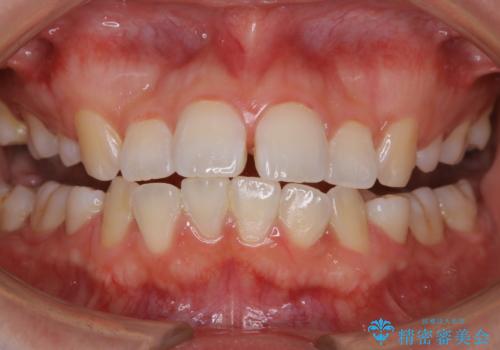

古くからの磨き残しや、歯石などにより、歯肉に炎症がみられ、かなり汚れが多く付着していました。PMTC60分コースで徹底的に汚れをおとしました。施術後の歯肉に出血が見られますが、次第におさまります。